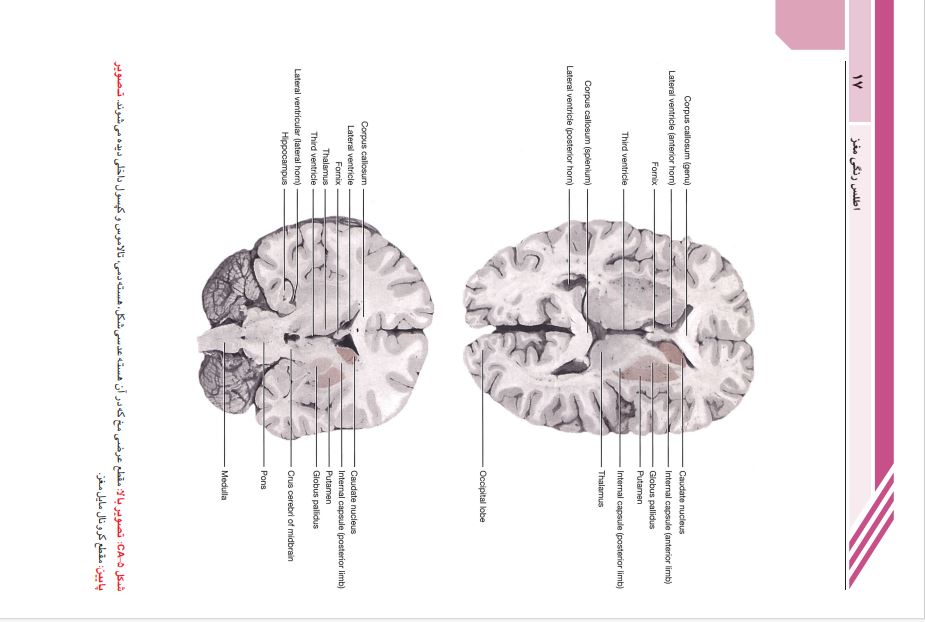

این کتاب ترجمه ی ویرایش نهم نوروآناتومی بالینی اسنل است.. این کتاب دربرگیرنده ی پایه ای ترین نکات علمی نوروآناتومی است که برای حرفه پزشکی ضروری است. در این ویرایش نویسنده ی کتاب تغییر یافته است. مطالب هر فصل مرور و ویرایش شده تا نکات نوروآناتومی به بهترین نحو ارائه شوند. تصاویر قبلی کتاب به روز شده و رنگ بندی آن ها تغییر یافته تا مطالب ارائه شده در هر تصویر گویاتر شوند.تصاویر MRI و میکروگراف های بافت شناسی با کیفیت بالا تهیه شده اند تا اطلاعات بصری دقیق تری ارائه دهند.

مطالب کتاب در 670 صفحه به ترتیب زیر نگارش شده است:

__فصل1:مقدمه و سازمان دهی دستگاه عصبی

__فصل2: نورون ها و نوروگلیا

__فصل3:رشته های عصبی و عصب دهی محیطی

__فصل4:نخاع و راه های صعودی, نزولی و بین قطعه ای

__فصل5:ساقه مغز

__فصل6:هسته های اعصاب مغزی

__فصل7:مخچه و ارتباطات آن

__فصل8:تشکیلات مشبک و دستگاه لیمبیک

__فصل9:هسته های قاعده ای(گانگلیون های قاعده ای)

__فصل10:تالاموس

__فصل11:هیپوتالاموس

__فصل12:دستگاه عصبی خودکار

__فصل13:مخ

__فصل14:ساختار و مناطق عملکردی قشر مغز

__فصل15:مننژ ها

__فصل16:دستگاه بطنی و مایع مغزی-نخاعی

__فصل17:خونرسانی مغز و نخاع

__فصل18:تکوین دستگاه عصبی